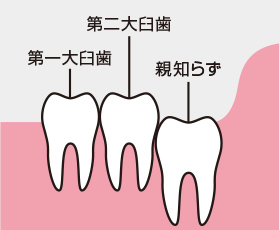

1.正常に生えているタイプ

他の歯と同じように使用することが可能